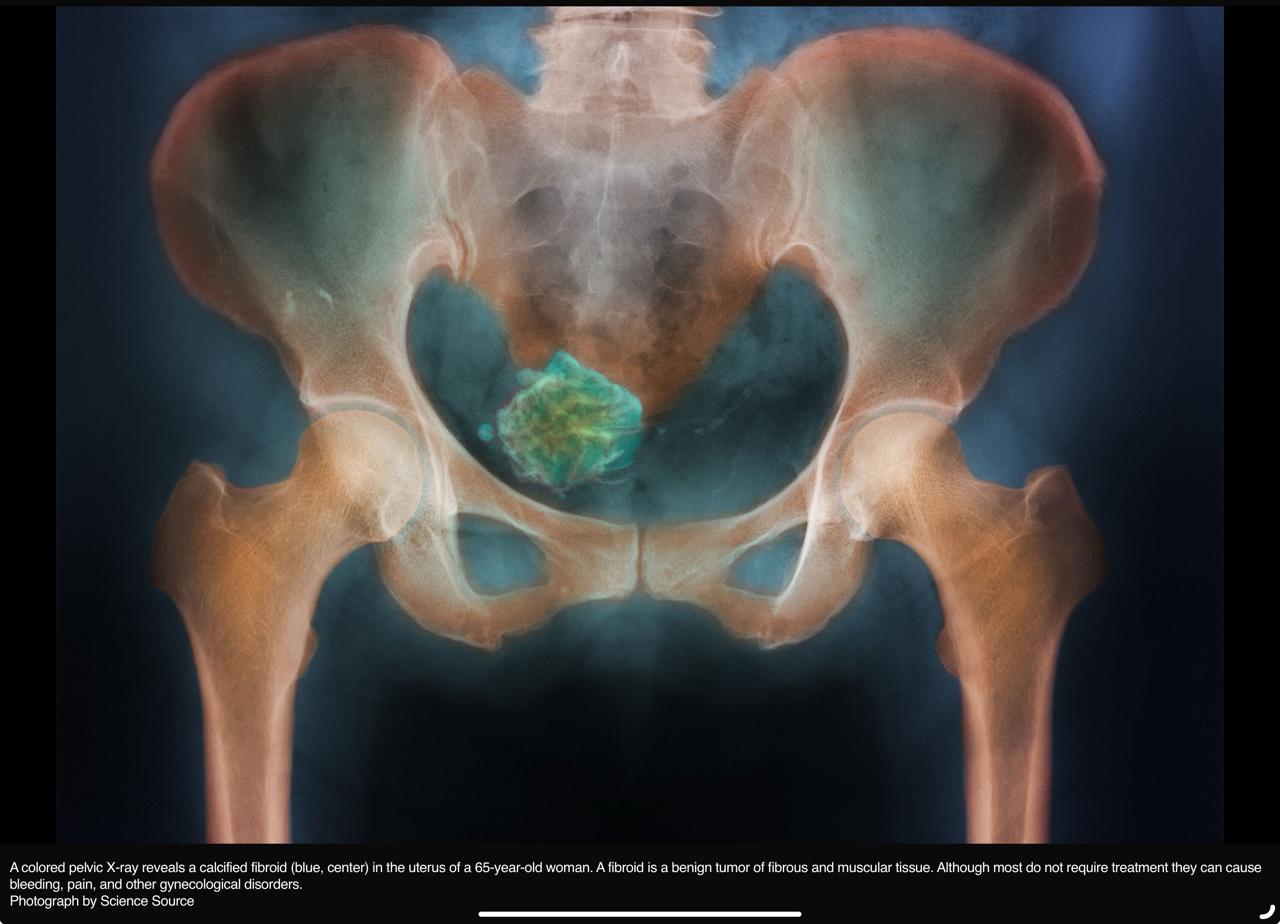

Fibroids are tumors that grow in the uterus (womb). They are benign, which means they are not cancerous, and are made up of muscle fibre. Fibroids can be as small as a pea and can grow as large as a melon. It is estimated that 20-50% of women have, or will have, fibroids at some time in their lives. They are rare in women under the age of 20, most common in women in their 30s and 40s, and tend to shrink after the menopause.